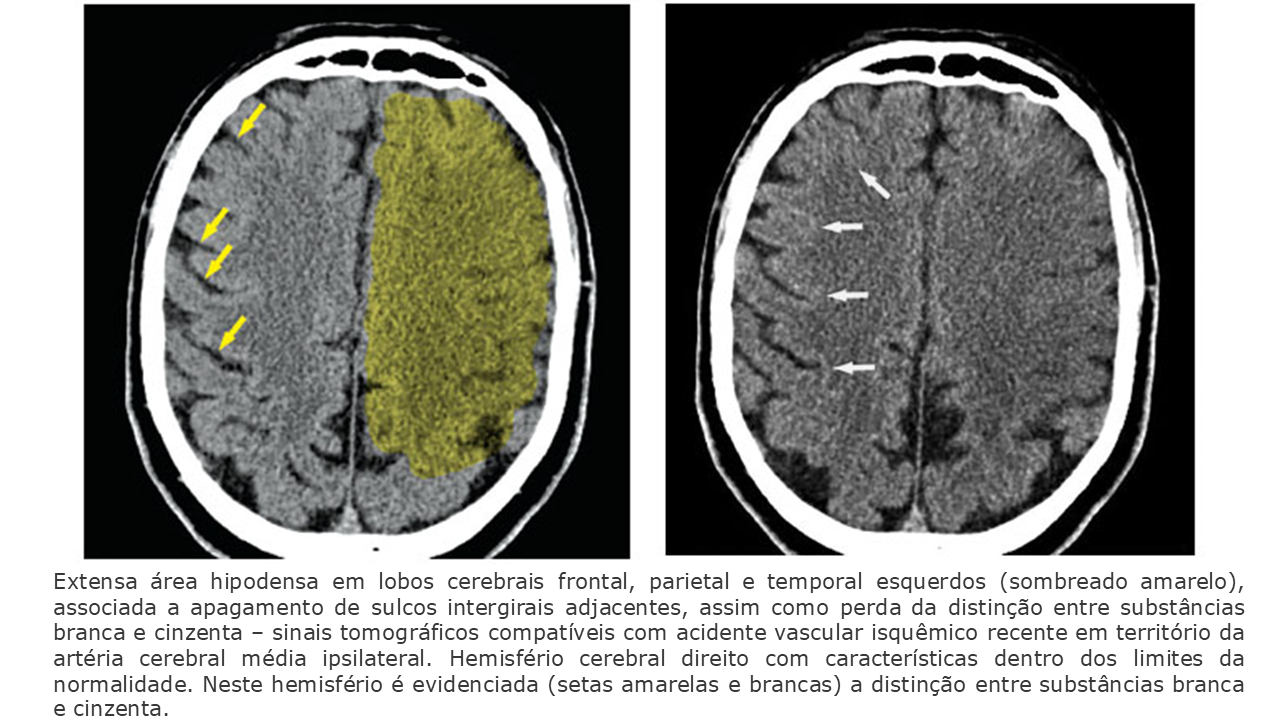

Áreas mais evidentes de hipodensidade (baixa atenuação) na região do infarto.

Edema citotóxico → aumento de volume local, compressão de sulcos e desvio discreto da linha média.

Hipodensidade bem definida no território vascular acometido.

Edema vasogênico importante → pode causar efeito de massa (desvio de linha média, compressão ventricular).